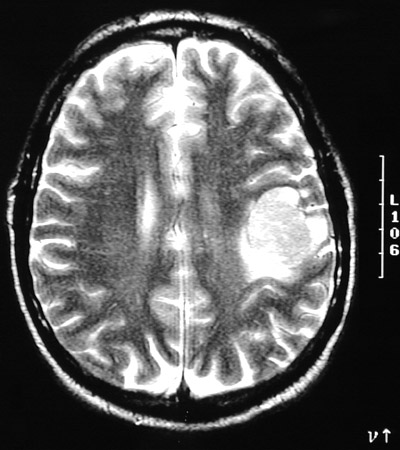

| These MRI scans in axial view, T2 weighted above and FLAIR below, demonstrate an enhancing solitary mass with minimal adjacent edema. This is a solitary metastasis from a pulmonary adenocarcinoma. In adults, metastases are more common than primary brain tumors. Typical primary sites include lung, breast, and kidney. |